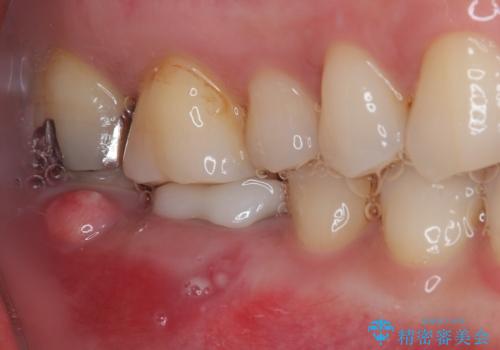

- 奥歯から膿が出てくることを気にして来院された患者様です。

診察より、奥から2番目の歯が割れている可能性が非常に高いため、まずは奥から2番目の歯の状態を診断することとしました。

クラウンを外したところ、目視でも確認できる破折線が認められたため、抜歯することとしました。

抜歯後も膿の出口が消えず、一番奥の歯を診察したところ神経組織の反応がなかったため、根管治療を行うこととしました。

一番奥の歯は歯肉から露出している高さが少なく、クラウンを装着する不十分であったため、歯冠長延長術を行うこととしました。